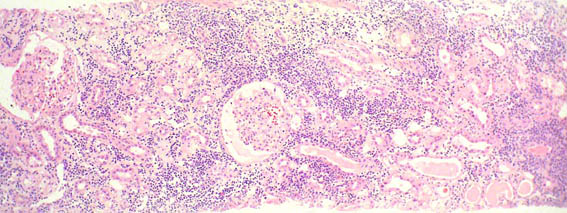

Figure 3. H&E, X200.

Figure 4. H&E, X100.